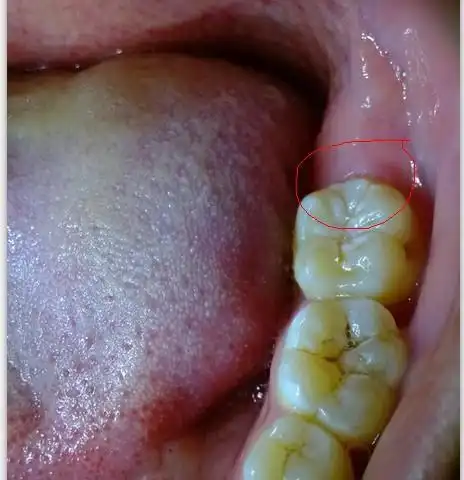

长智齿了怎么办?

什么样的智齿一定要拔掉?

下颌阻生智齿危害的剖析